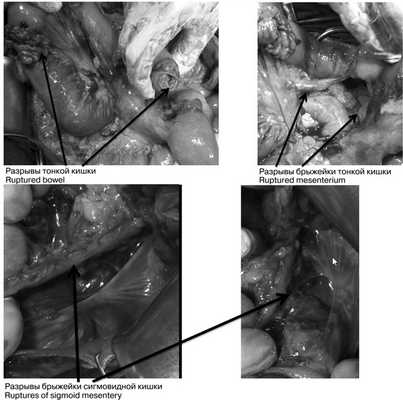

При динамическом наблюдении отмечено нарастание явлений геморрагического шока. С учетом клинико-инструментальной картины заболевания закрытой травмы живота с повреждением внутренних органов и продолжающимся внутрибрюшным кровотечением в экстренном порядке выполнена лапаротомия. Во время доступа в брюшную полость выявлено, что кожа и подкожная клетчатка полностью отсепарированы от подлежащего слоя прямых и косых мышц, имбибированных кровью из-за размозжения (межмышечная гематома) на всем протяжении доступа. Множественные более мелкие гематомы в подкожной клетчатке. В брюшной полости во всех отделах большое количество крови и сгустков (1800 мл), кровь аспирирована с помощью аппарата CellSaver. Продолжающегося активного кровотечения не выявлено. При ревизии органов брюшной полости: в проекции V—VI сегментов правой доли печени по краю выявлена подкапсульная гематома размером около 6×2 см, не пульсирующая, в объеме за время операции не увеличилась. Других повреждений печени по диафрагмальной и висцеральной поверхностям не установлено; на расстоянии 30, 40 и 45 см от связки Трейца 3 разрыва стенки тощей кишки с вскрытием просвета и 1 десерозированный участок. В области разрывов кишки также отмечены участки повреждения брыжейки тонкой кишки (рис. 3), Рис. 3. Разрывы петель тонкой и толстой кишки (интраоперационные фотографии). откуда продолжалось кровотечение. На расстоянии 60 см от связки Трейца выявлен полный поперечный разрыв тощей кишки с разрывом брыжейки кишки до уровня ее корня и активно продолжающимся кровотечением из сосудов брыжейки. Гематома в области брыжейки поперечной ободочной кишки, просвет кишки не вскрыт, гематома в размерах не увеличивается. Помимо этого гематома околокишечной клетчатки вдоль нисходящей ободочной кишки и сигмовидной кишки, брыжейка которой на уровне дистальной трети разорвана; сама сигмовидная кишка в области разрыва брыжейки не изменена, спастически сокращена, просвет не вскрыт, серозная оболочка обычной окраски с небольшими петехиальными кровоизлияниями из-за травмы. Обширная забрюшинная гематома по левому латеральному каналу с распространением на парааортальное клетчаточное пространство и корень брыжейки тонкой кишки. Париетальная брюшина в области левого латерального канала также разорвана, визуализирован левый мочеточник, без повреждений (моча концентрированная, макрогематурии нет). В области боковой стенки живота со стороны париетальной брюшины разрыв стенки размером около 10×5 см с повреждением прямых и косых мышц живота и продолжающимся низкоинтенсивным кровотечением из мышечных сосудов.

При рентгенографии органов брюшной полости при поступлении: газ и плотное содержимое по ходу толстой кишки на всем протяжении; в мезогастрии единичные пневматизированные петли тонкой кишки, диаметром 3,3 см с нечеткими уровнями жидкости. Заключение: функциональный фон.

В экстренном порядке выполнена диагностическая лапароскопия: в брюшной полости мутный геморрагический выпот до 300 мл во всех отделах живота, на висцеральной брюшине мезогастральной области налет фибрина. На расстоянии 80 см от илеоцекального угла сквозной дефект тонкой кишки с вывернутыми краями размером 3×2 см. Принято решение о конверсии — выполнена широкая срединная лапаротомия. В брюшной полости 450 мл геморрагического содержимого с примесью кишечного отделяемого. В 80 см от илеоцекального угла определяются 3 линейных разрыва подвздошной кишки диаметром до 1,5 см (рис. 5). Рис. 5. Множественные разрывы стенки тонкой кишки (интраоперационные фотографии). Брыжейка тонкой кишки с множественными поверхностными разрывами, кровоподтеками, гематомой (рис. 6). Рис. 6. Разрыв брыжейки тонкой кишки (интраоперационная фотография). В верхней трети сигмовидной кишки дефект серозно-мышечного слоя размером 2×1 см. При дальнейшей ревизии повреждений желчного пузыря, желудка, начального отдела двенадцатиперстной кишки не выявлено. Выполнена резекция около 15 см участка подвздошной кишки с тремя разрывами. Сформирован энтероэнтероанастомоз конец в конец. Произведена назоинтестинальная интубация. Выполнено ушивание дефекта стенки сигмовидной кишки. Произведено дренирование брюшной полости в полость малого таза, правое подпеченочное пространство и в левый латеральный канал.